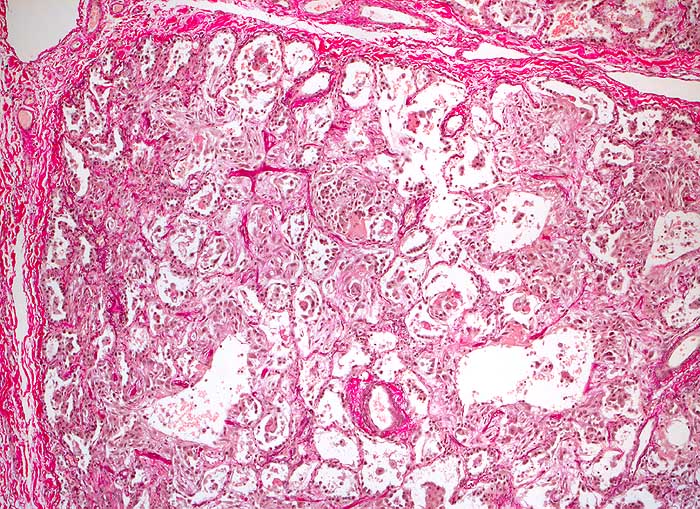

PathoPic – image database / PathoPic ID 6126 - diffuser Alveolarschaden proliferatives Stadium

diffuser Alveolarschaden proliferatives Stadium

Bild eines ausgeprägten diffusen Alveolarschadens (proliferatives Stadium) mit intraalveolären und septalen lockeren Fibroblastenproliferaten. Beginnende Fibrose.

V.a. RSV-Pneumonie, ARDS. St.n. Knochenmarkstransplantation vor 6 Monaten.

Histologie

50